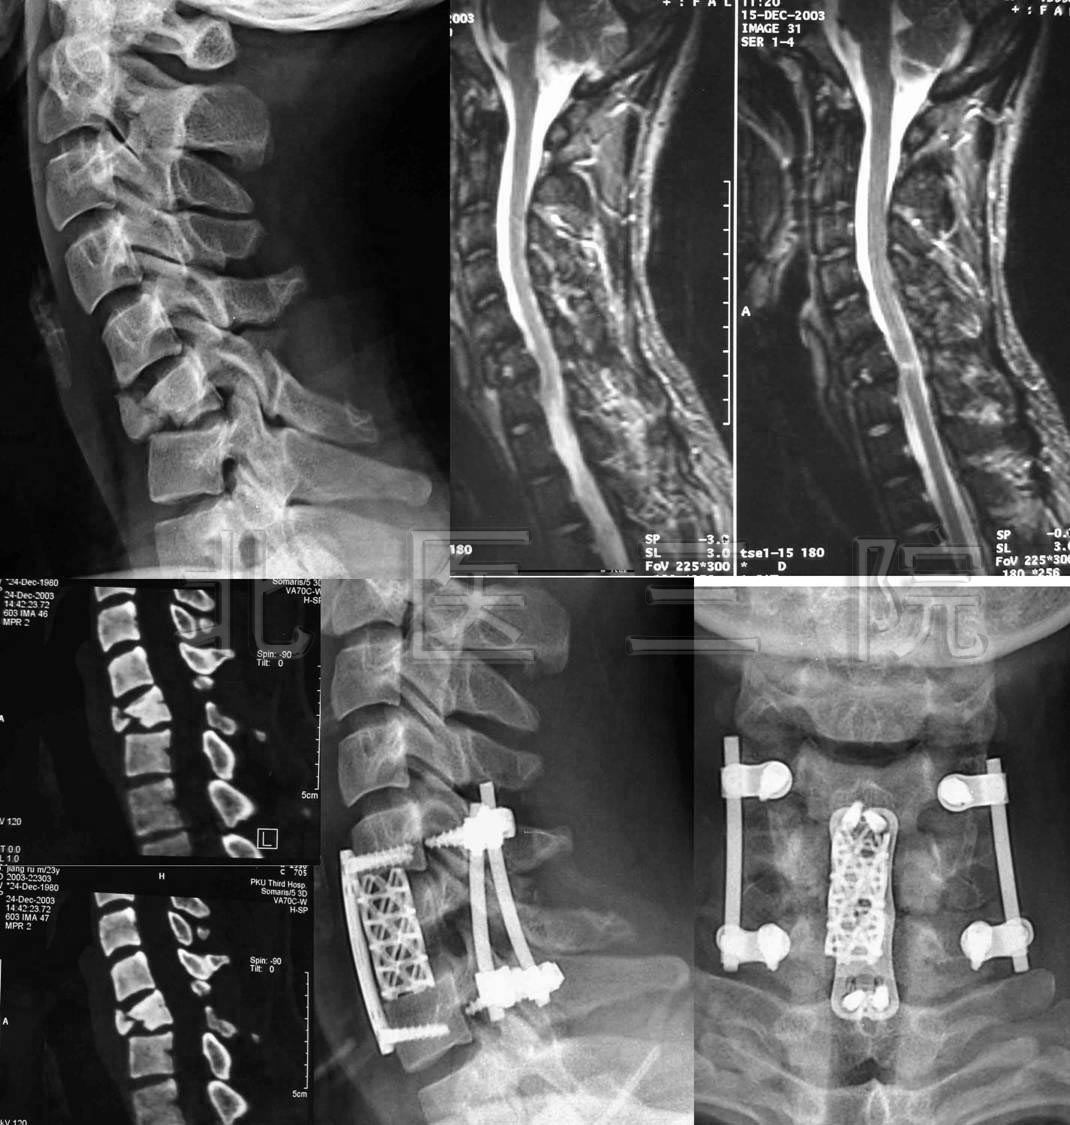

图1:21岁美国大学生,车祸致颈、腰椎多处骨折,四肢不全瘫。

FIGURE 1:A 21-year-old American college student, multiple fractures

of cervical and lumber spine in a car accident, ASIA C incomplete paralysis.

图2:手术后一周下地行走。

FIGURE 2: standing and walking one week after operation

图3:手术后9个月复查

FIGURE 3: Nine months after operation

10.C6陈旧性骨折脱位

男,23岁,70天前车祸伤,当时有昏精迷史,2天后苏醒,

感觉颈部疼痛,右前臂与右手掌尺侧感觉过敏,左手指不能

活动,双下肢感觉活动正常保守治疗后症状加重,转我院手

术治疗症状缓解

11.L3爆散性骨折脱位

男,38岁,L3爆散性骨折脱位伴尾神经完全损伤3周入院

术后可乘坐轮椅